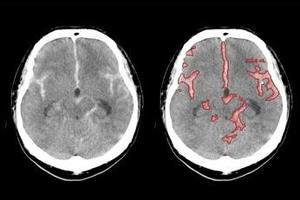

「医療クラウドサービス」は,「SYNAPSE LEAD Cloud」からクラウドサーバーにアップロードされた画像に対し,選択した読影支援機能の解析結果をビューワ上で参照できるサービス。ユーザー登録後,専用ポータルサイトから「胸部X線CADサービス」や「肺結節検出サービス」など,5つの解析機能の中から必要なものを選択するだけで,簡単に利用できる。料金プランは,利用回数に応じた従量課金と,一定期間利用できる定額利用の2種類を用意しており,導入コストを抑えながら,目的や運用に応じた柔軟な活用が可能である。さらに,本格導入前に無料トライアルから利用を開始することもできる。

頭部高吸収/低吸収強調フィルタサービス*9 |

*9 頭部高吸収/低吸収強調フィルタサービスは,画像処理プログラム FS-AI683型で実現している。